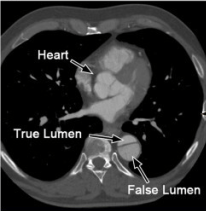

The heart is an incredibly intricate four-chambered structure that pumps blood to the lungs and through the body intrinsically; that is, it possesses automaticity. Deoxygenated blood travels from the superior and inferior vena cavas to the right atrium, to the right ventricle, to the lungs, to the left atrium, to the left ventricle, and finally the aorta, all mediated through the cardiac cycle. Importantly, the heart possesses valves and supporting structures that prevent the back flow of blood.